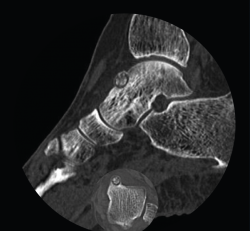

Se trata de una mujer de 64 años que presenta dolor en el tobillo izquierdo de 36 meses de evolución; la paciente refiere un dolor nocturno para el que precisa toma de salicilatos. Se realizó una radiografía que no evidenció lesiones óseas, la TAC nos informa de una lesión lítica yuxtacortical en el astrágalo de 8 mm de diámetro con calcificaciones de aspecto condroide en el centro de la misma (Figura 1). La RMN sugería un OO, ya que presentaba una tumoración ósea en el cuello del astrágalo con cambios inflamatorios periféricos y abundante edema óseo difuso del astrágalo (Figura 2).

Figura 1. Tomografía axial computarizada inicial donde se observa una lesión yuxtacortical en el astrágalo de 8 mm de diámetro.